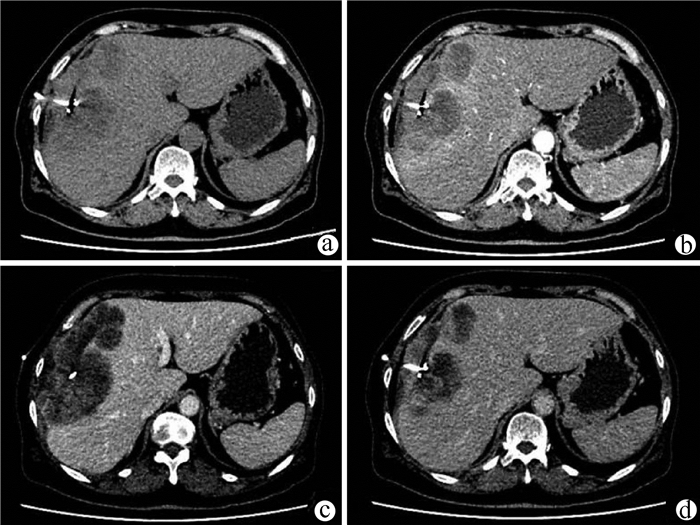

Jaundice and portal hypertension caused by hepatic epithelioid hemangioendothelioma: A case report

Ruihua ZHANG, Tingting QIN, Yueming SHAO, Yu ZHANG, Yang WANG, Xiaoyu WEN

2021, 37(7): 1662-1664. DOI: 10.3969/j.issn.1001-5256.2021.07.036

Abstract(1181) HTML (235) PDF (2873KB)(100)

Abstract: